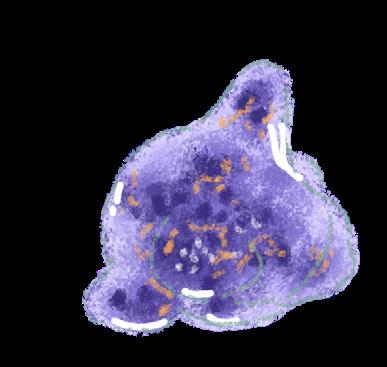

Naegleriafowleri, commonly referred to as the “brain-eating amoeba,” is an amphizoic amoeba that exists as both a freefloating organism and a parasite.1,2 Infection by N. fowleri is deadly in humans, exhibiting a fatality rate of 97%.3 As a free-living amoeba, N. fowleri can transition between three phenotypes depending on its environment: trophozoite, flagellate, and cyst. Under nutrient-rich conditions where N. fowleri can proliferate, it assumes a trophozoite form, which is reproductively active and infectious to humans. During this stage, it can cause primary amebic meningoencephalitis (PAM), a rapidly fatal infection of the central nervous system (CNS). Conversely, under nutrient-poor conditions, N. fowleri can temporarily transform into its flagellate form. Though this form is unfavourable for growth, it facilitates long-distance travel to search for nutrients.2,4 Finally, under environmental stress, such as the absence of water and lower temperatures, N fowleri switches into its metabolically inactive cyst form, which can withstand temperatures from 0°C to 65°C.4

The pathogenic mechanisms of N. fowleri infection consist of phagocytosis, secretion of proteases, phospholipases, and pore-forming proteins (PFPs). N. fowleri utilise structures resembling suction cups known as amoebastomes to consume neurons through contact-dependent phagocytosis, leading to the progressive destruction of brain tissue.7 The amoeba also prompts the release of PFPs, membrane-bound proteins that degrade the stability of the host cell membrane, causing cell death.9 Additionally, N. fowleri can cross the blood-brain barrier (BBB) by destroying the tight-junction proteins (TJPs) between host endothelial cells. This mechanism involves secreting cysteine protease that degrade TJPs and modify the cell’s cytoskeleton, breaking down the BBB.8 The amoeba also uses phospholipase enzymes to destroy neuronal myelin by degrading phosphatidylcholine, a major structural component of the myelin sheath.

The presence of trophozoites prompts macrophages and other immune cells to release cytotoxic molecules, resulting in necrosis of olfactory tissues.5,9 Further, N. fowleri has evolved to evade immune mechanisms and has become resistant to destruction by cytolytic immune processes.9 Microglia, the neuronal immune cells, activate immune signalling pathways in response to the amoeba for the secretion of cytokines. However, the proteases and signalling molecules secreted by N. fowleri can cause microglial lysis.9 As amoebal growth within the host progresses, a positive feedback loop of leukocytes and pro-inflammatory cytokines is initiated, resulting in uncontrollable CNS inflammation.9 This inflammation prevents the CNS from controlling the infection, leading to fatal haemorrhage and edema.9